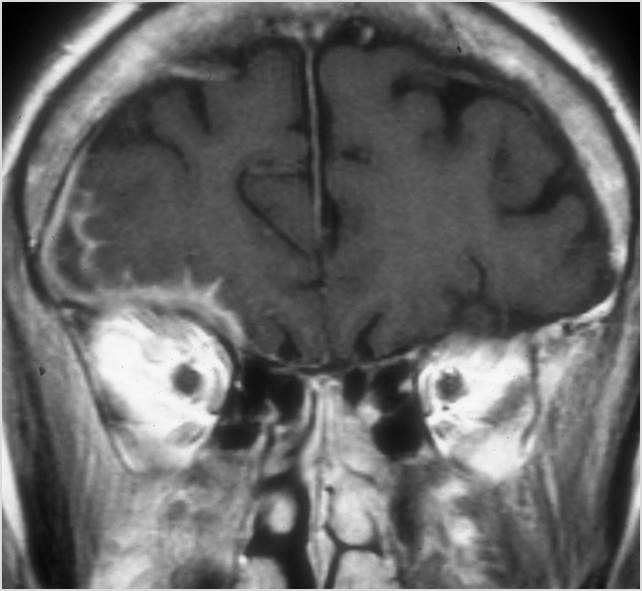

Orbits

The extraconal orbital fat is abnormal. [Yes/No]

There is a subperiosteal abscess or edema along the medial wall, roof or floor of the orbit. [Yes/No]

The extraocular muscles are swollen or otherwise abnormal. [Yes/No]

There is bone erosion along the walls of the orbit. [Yes/No]

The intraconal orbital fat is infiltrated. [Yes/No]

The orbital apex and the superior and inferior orbital fissures are infiltrated. [Yes/No]

The superior and/or inferior ophthalmic veins are dilated or thrombosed. [Yes/No]

Eyes

Proptosis is present. [Yes/No]

The optic nerve is stretched in appearance. [Yes/No]

The posterior aspect of the globe is tented in appearance. [Yes/No]

The uveal scleral margin of the globe is swollen or enhancing abnormally. [Yes/No]

Signs of tension orbit or endophthalmitis are present. [Yes/No]